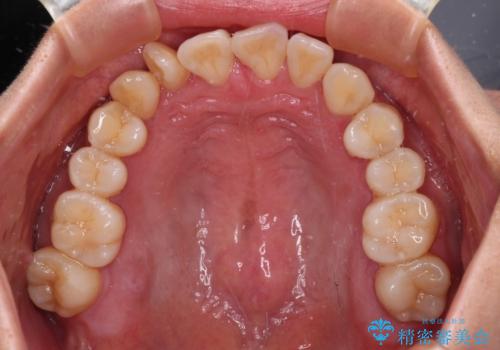

【モニター】上顎前突と奥歯の鋏状咬合 補助装置を用いたインビザライン矯正治療

- 前歯の歯列不正と奥歯の咬みにくさを気にして来院された患者様です。

インビザラインでの矯正治療を希望されていましたが、奥歯の咬み合わせがインビザライン単独では改善困難と判断されたので、補助装置を併用することとしました。

上顎最後臼歯は極端に外側を向いており、下顎骨に対して上顎骨が前方に位置していたため、補助装置により最後臼歯を一気に内側に引き込むとともに、上顎臼歯を後方移動させ、奥歯の咬み合わせが改善した後に、上下インビザラインにより歯列全体を整えていくこととしました。

奥歯の咬み合わせを事前に望ましい位置に改善したことで、インビザライン単独では改善が最も困難な状況を排除することができ、非常に理想的な仕上がりとなりました。